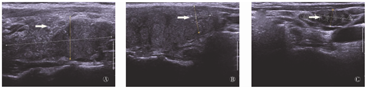

超声提示甲状腺左叶下极见1.4 cm×1.2 cm中等回声区,边界模糊,其内见数个强回声点。右叶内见密集强回声点,中上部明显。右侧颈部可见多个肿大淋巴结,较大者约1.7 cm×0.8 cm,内呈囊实混合回声伴多个强回声点(图1)。